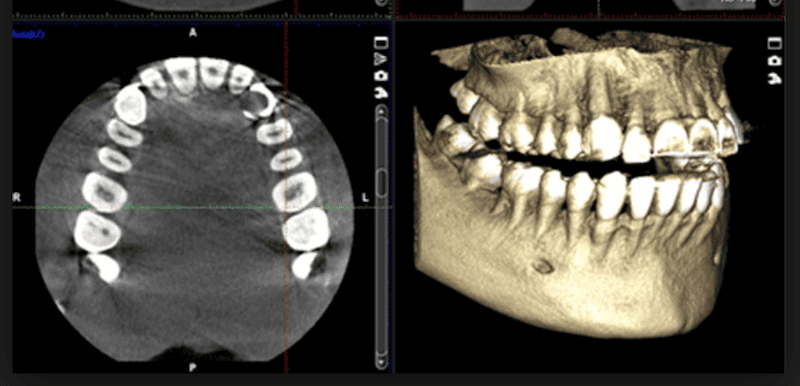

We make the decision with a clinical exam + X-rays. Normally, we start with a panoramic; if there are important doubts (for example, a nearby nerve), we use 3D imaging (CBCT) to decide with precision.

imagen 3D (CBCT)

Reference image

3. Does the root appear very close to the nerve on the panoramic X-ray? → We assess with CBCT to fine-tune the plan and choose the safest technique.

The panoramic X-ray is the first step. CBCT (3D) isn’t ordered “just in case,” but when it changes decisions: for example, to see distances to the inferior alveolar nerve or the shape of the roots and adapt the technique. That’s how we make surgery more predictable and conservative.

When the panoramic X-ray suggests proximity to the nerve or the anatomy is unclear and we need to determine technique and risks with precision.